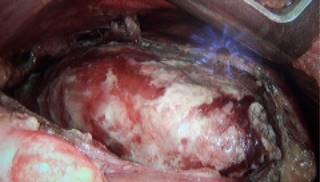

Mujer de 50 años, originaria de Cuernavaca, estado de Morelos, de ocupación campesina. Antecedentes de infección de vías aéreas de repetición. Inicia padecimiento actual dos meses previos a su ingreso con disnea progresiva, tos seca, dolor precordial y rinorrea con tratamientos múltiples no especificados sin mejoría. Dos semanas previas a su ingreso presenta además ortopnea y edema de miembros inferiores, debido a ello es referida al Instituto Nacional de Enfermedades Respiratorias Ismael Cosío Villegas de la Ciudad de México. A su ingreso los signos vitales eran TA 110/70 mmHg, FC 98 X’, FR 28 X’, temperatura 36.8 oC, saturación 90%. Campos pulmonares con hipoventilación basal bilateral y ruidos cardíacos disminuidos en intensidad. Se realizó radiografía de tórax encontrando datos de cardiomegalia y derrame pleural bilateral (Figura 1), se hace tomografía contrastada de tórax, donde se observa derrame pericárdico y derrame pleural bilateral (Figura 2). Ecocardiograma con pericardio engrosado de 9 mm e hiperrefringente con derrame de 500 cm3, colapso parcial de cavidades derechas y alternancia eléctrica en el electrocardiograma con variación en el llenado mitral > 35%. Debido a que no se contaba con diagnóstico etiológico al momento, se decidió realizar toracoscopia derecha diagnóstica con ventana pericárdica. Debido a los hallazgos quirúrgicos de líquido pericárdico purulento de 600 mL, no fétido (Figura 3) con adherencias firmes de pericardio a miocardio en algunos segmentos, pulmón y pleura y derrame pleural cetrino de 300 mL, se decidió convertir a toracotomía posterolateral y realizar pericardiectomía parcial para adecuado lavado, drenaje y desbridamiento de tejido necrótico y fibrina (Figura 4). Los cultivos de líquido pericárdico y biopsia de pericardio fueron negativos. No se hizo estudio citoquímico de líquido pericárdico debido a sus características purulentas. Los estudios para tuberculosis en biopsia y líquido pericárdico tinción Ziehl-Neelsen, baciloscopia y una prueba rápida de reacción en cadena de la polimerasa y de resistencia a rifampicina (GeneXpert MTB/RIF)MR para formas extrapulmonares de la tuberculosis fueron negativos. El galactomanano también fue negativo. Reporte de patología de pericardio resecado: pericarditis fibrinosa no granulomatosa con datos histológicos que sugieren etiología fímica, sin datos de malignidad. Ante la negatividad de todos los estudios se realizó inmunodifusión de histoplasma en orina (antigenuria), que resultó positiva. Posterior a estos estudios se indicó tratamiento con anfotericina B por el servicio de infectología durante tres semanas, después de lo cual se tomó control de antígenos en orina, los cuales fueron negativos y se decidió suspender tratamiento. Mostró evolución con mejoría clínica. Tomografía contrastada de control para delimitación de estructuras cardíacas sin datos de derrame pericárdico y escaso derrame pleural derecho (Figura 5). Fue egresada del instituto con seguimiento al mes, con adecuada evolución sin recaídas al momento. Debido a la pandemia se dio seguimiento por vía telefónica con adecuada evolución a los tres meses.

El abordaje por toracoscopia es el de elección para realizar una ventana pericárdica en un paciente con derrame pericárdico, aunque en nuestro caso al encontrar adherencias firmes del pericardio al miocardio en algunos segmentos y extensas zonas de material necrótico y fibrinopurulento se optó por un procedimiento abierto para adecuado desbridamiento y seguridad en la paciente y con ello presentar algún accidente. En estos casos siempre se recomienda el drenaje; existe una mortalidad global de 8% que puede aumentar cuando existen adherencias por una pericarditis. La toracotomía anterior también es útil para el abordaje del pericardio.8